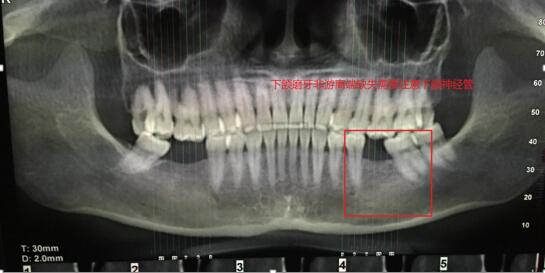

案例一:下頜磨牙缺失(非游離端)

吳X,女,46歲;主訴: 左下后牙缺失3月余,影響美觀?,F(xiàn)病史:左下后牙3個(gè)月前因牙體治療失敗在我院頜面外科拔除,現(xiàn)要求種植修復(fù)。既往史:否認(rèn)系統(tǒng)病史。檢查:36缺失,拔牙創(chuàng)愈合良好,缺失間隙近遠(yuǎn)中寬度7mm,頜齦距離正常,頰舌向?qū)挾燃s8mm。輔查:口腔CBCT顯示36可用牙槽骨高度(牙槽嵴頂?shù)较骂M神經(jīng)管)約18-19mm,頰舌側(cè)寬度12mm,骨質(zhì)正常,無(wú)疏松影像,鄰牙根尖周無(wú)暗影。 診斷: 36牙列缺損。治療計(jì)劃:種植義齒修復(fù)36牙列缺損。 處理: 1. 與患者說(shuō)明種植牙修復(fù)的治療過(guò)程,注意事項(xiàng)和費(fèi)用,患者同意種植修復(fù)。 2. 血常規(guī)檢查,全口牙潔治。 3. 患者口內(nèi)藻酸鹽...